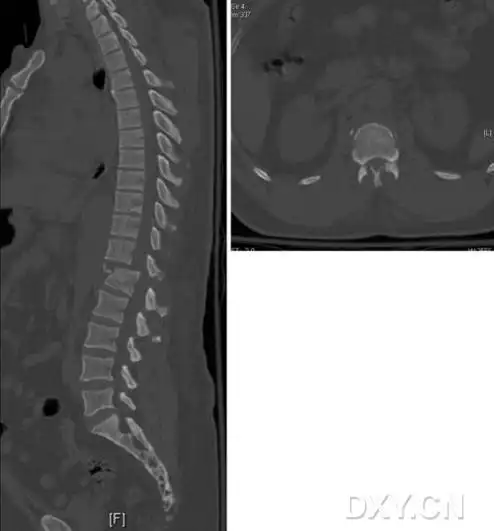

上了岁数腰痛,不知不觉的脊椎骨折,严重吗,怎么办?

腰1左侧,腰2双侧,腰3-4右侧横突骨折,腰1棘突骨折

多发腰椎横突骨折一例,需要手术吗

胸腰椎粉碎性骨折合并神经损伤 - 好大夫在线